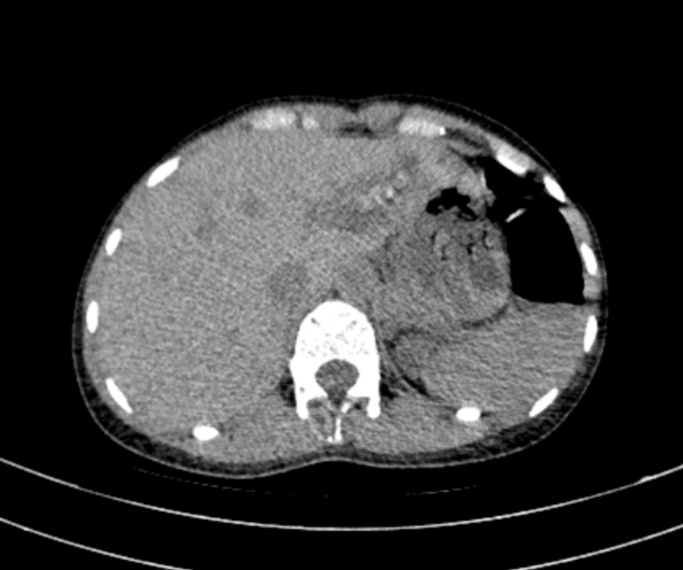

Bệnh nhân nữ 67 tuổi xuất hiện đau hạ sườn phải từng đợt nhiều năm, Mỗi lần đau thường kèm theo sốt, vàng da. BN đã đi khám ở tuyến trên được chẩn đoán tắc mật do sỏi ống mật chủ và sỏi trên gan. BN được chỉ phẫu thuật và quyết định mổ tại BVĐK Hải Dương. Chúng tôi sau khi xem xét hồ sơ bệnh án đã quyết định thực hiện phẫu thuật nội soi tán sỏi OMC và sỏi trên gan kèm tán sỏi Laser. Ca mổ đã diễn ra vô cùng thuận lợi. Sau 2 tiếng ca mổ đã hoàn thành. Sỏi trên gan và sỏi OMC được tán nhỏ và lấy qua nội soi. Sau 10 ngày điều trị hậu phẫu bệnh nhân đã được ra viện.

Hình ảnh sỏi và BN sau mổ với vết mổ rất nhỏ